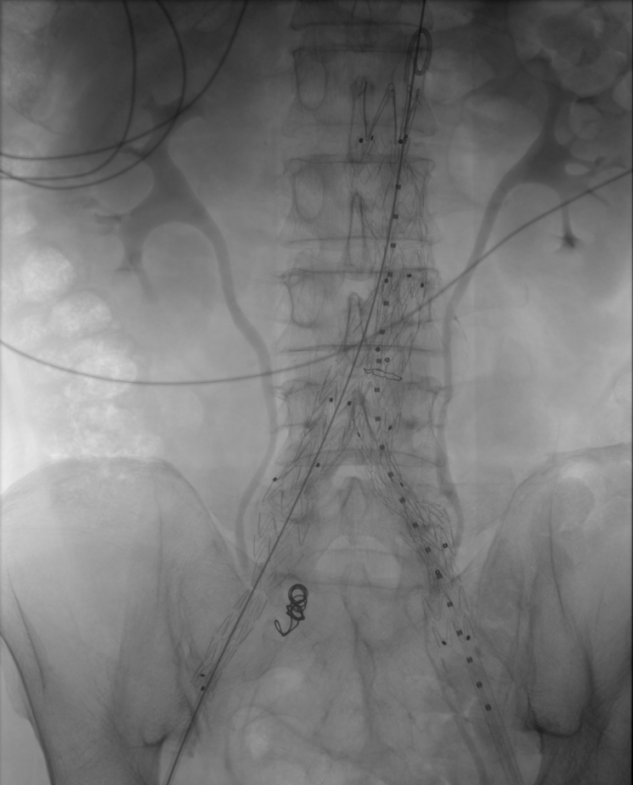

我院微创介入科易长虹副主任医疗团队在对患者病情进行综合评估后,制定治疗方案,11月7日为患者行腹主动脉瘤微创介入治疗。

▶ 腹主动脉造影,腹主动脉中下段呈瘤样扩张